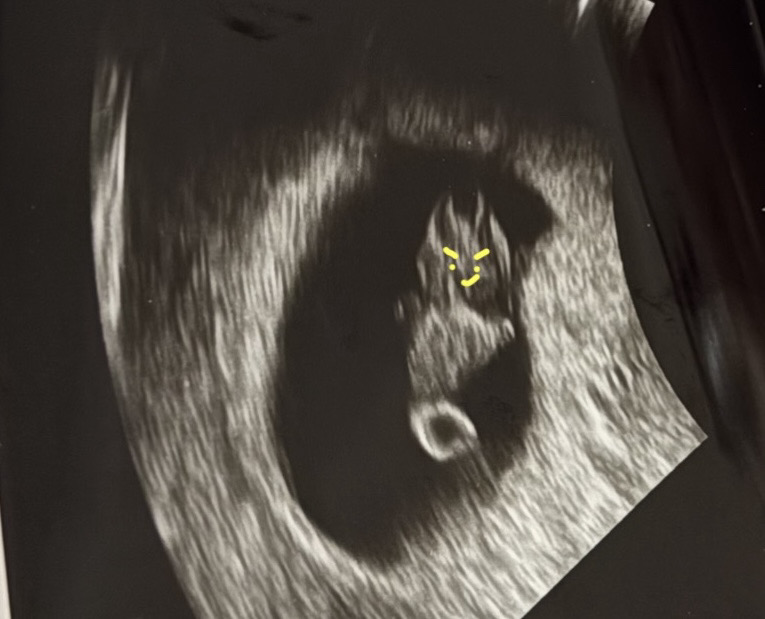

어제 그냥 갑자기 덩어리 혈이나오고 휴지에 첫날 생리피처럼 묻어나와서 바로 병원갔다왔네요ㅠㅠㅠㅠ 얼마나 식겁했는지 ㅠㅠㅠㅠ 피고임이 떨어져 나온거 같다구... 아기는 잘크고있다고 괜찮다고 하는데 진짜 심장이 터지는줄 알았어요.. ㅠㅠ하... 어제는 정신이 없어서 초음파를 자세히 못봤는데오늘 아침에 보니까 아기 악마가 뿅하고 있네욬ㅋㅋㅋㅋ찾아보니 뭐 머리뼈가 완전히 정리되지 않아서 초음파 각도에 따라 빛반사한거라고 ㅋㅋㅋㅋ웃겨서 눈코입 그려봤어욬ㅋㅋㅋ